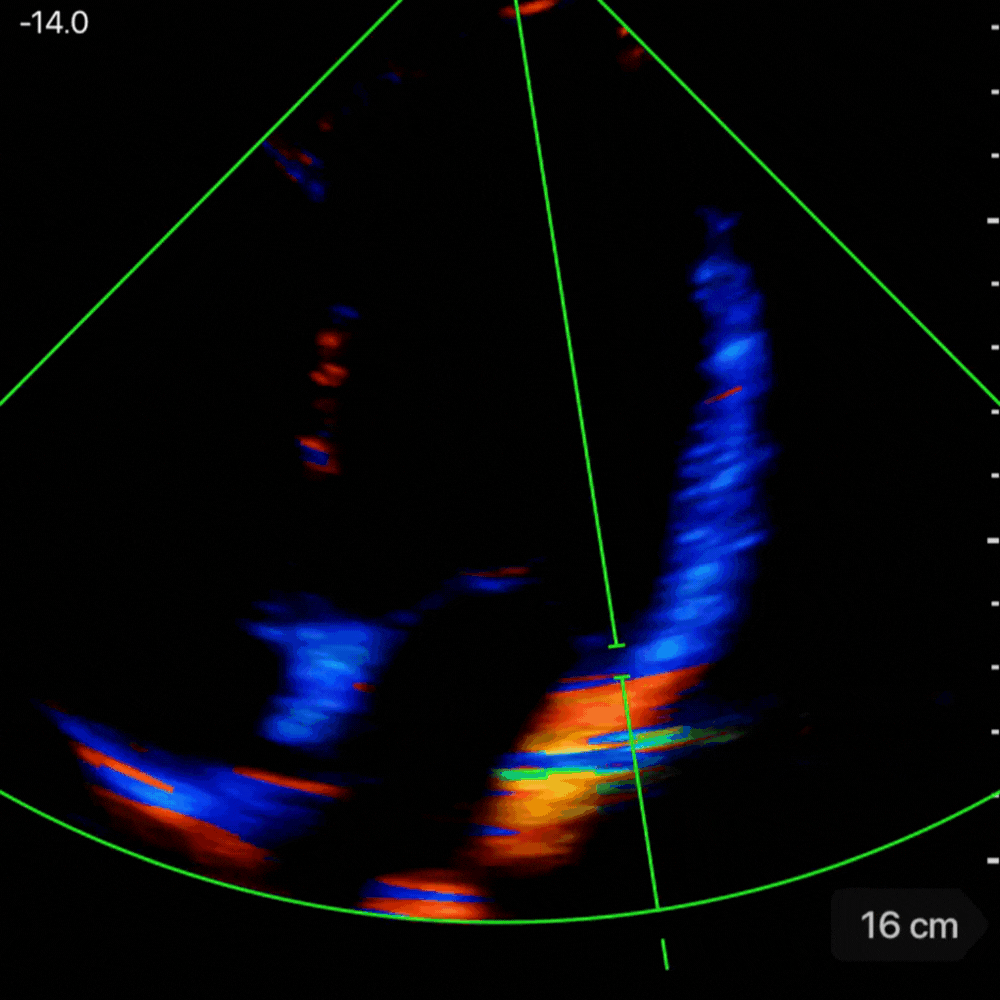

🔧 Comment mesurer E/E’

- Mesurer l’onde E comme décrit ci-dessus (si déja fait, la machine retient la valeur)

- En A4C, placer le curseur sur l’anneau mitral, en latéral

- Activer le mode Doppler tissulaire (TDI).

- Chercher la premiere onde négative apres le onde S' – c'est l'onde E’ (cf. vidéo/photo ci-dessous)

- Mesurer la vitesse maximale de E’. La machine fait le calcul du rapport pour vous.